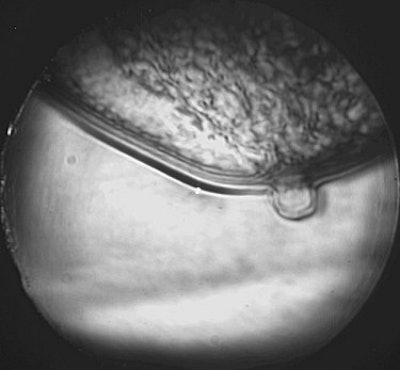

DUS uses a gray scale that correlates white with high sound transmission and dark with low sound transmission, making cysts look relatively white and solid masses look dark.

A fibroademona (above) and a ductal carcinoma (middle) as seen on diffractive ultrasound. Below, normal findings that highlight the different tissue layers in the breast. Images courtesy of Advanced Imaging Technologies.

On DUS, cystic lesions are round, oval, or lobular in shape, with circumscribed margins. Solid masses are oval, lobulated, or irregular in shape, with either circumscribed or ill-defined margins. Malignant tumors exhibit architectural distortion by distorting the pattern produced by the surrounding fibroglandular tissue.